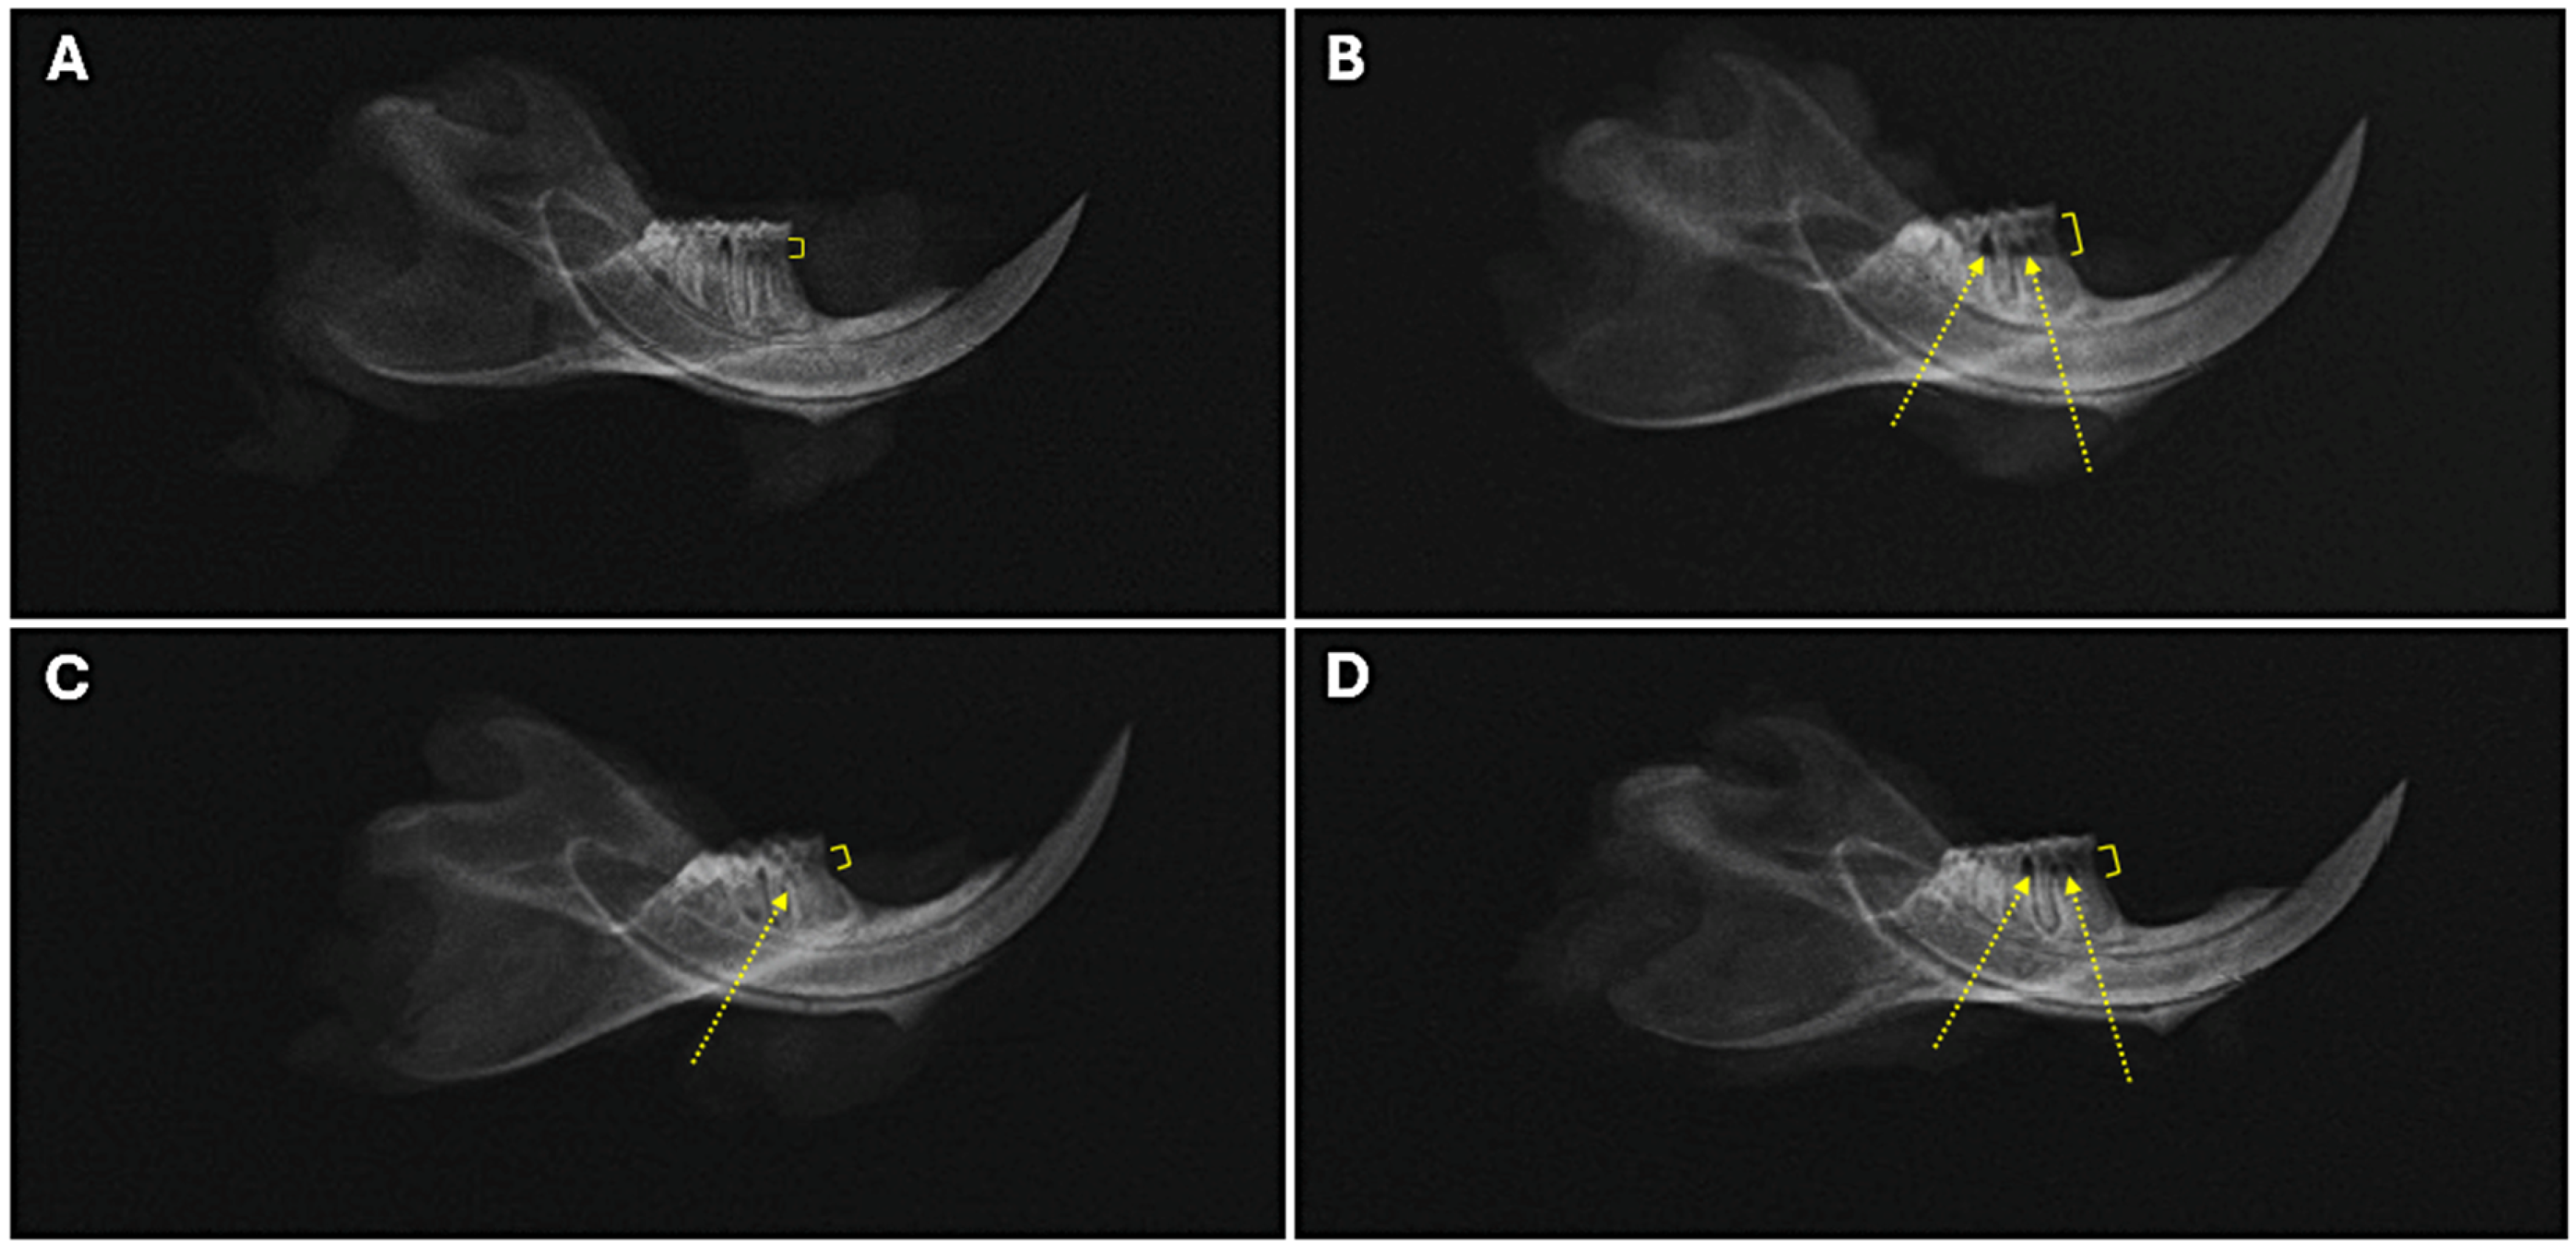

2.2. Bone Loss Assessment

2.3. Alveolar Bone Radiographic Analyses

4.7. Radiographic Assessment of Alveolar Bone Loss and Periodontal Bone Support